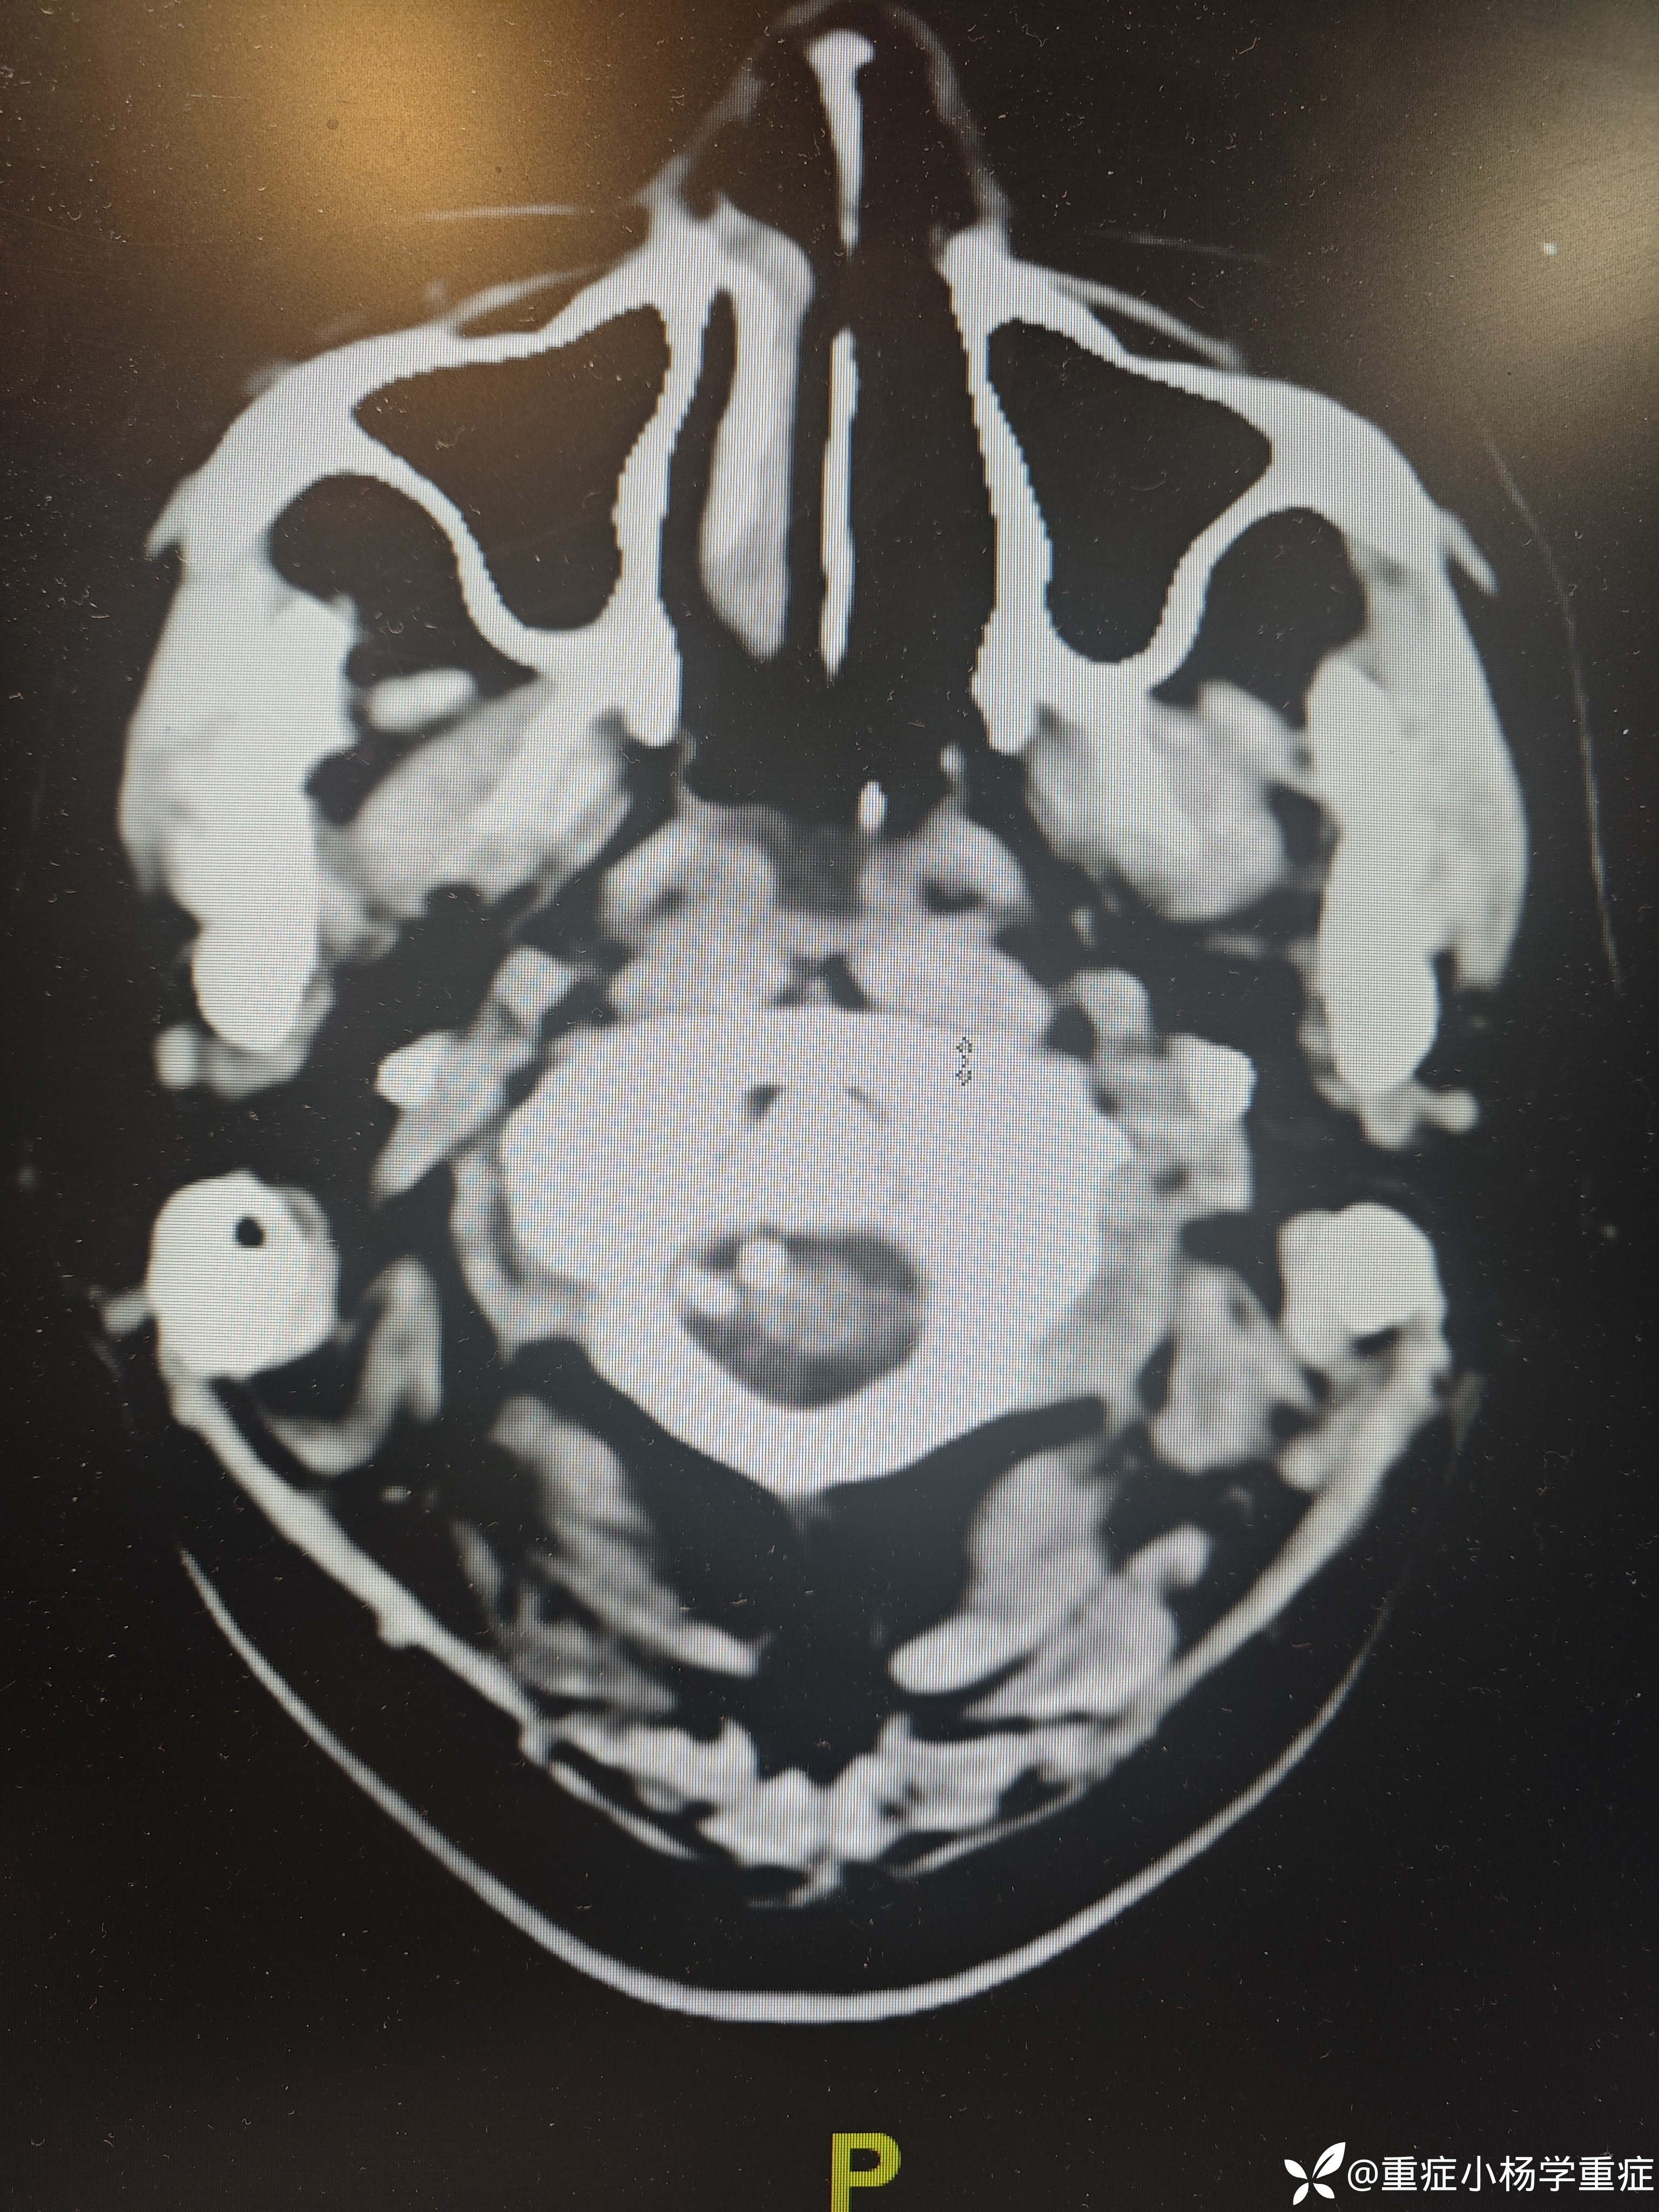

飞跃迷雾1 达人已点赞因“代:脑出血术后2月余,痰多伴呼吸困难1小时”入院。因头痛至医院检查ct提示蛛网膜下腔出血,后完善CTA提示脑血管畸形,至省内医院行介入栓塞后出现脑梗塞,考虑压迫延髓导致呼吸功能损伤,术后第二天予以气切,后出现四肢瘫痪,近期ct如下